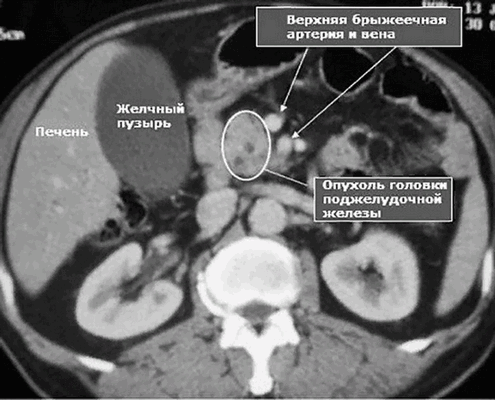

Рак поджелудочной железы на МРТ

Рак головки поджелудочной железы на МР-томограмме

На рисунке неоперабельная опухоль головки поджелудочной железы, блокирующая общий желчный и панкреатические протоки, окружающее верхнюю брыжеечную вену; видно увеличение регионарных лимфоузлов, единичные метастазы в печени